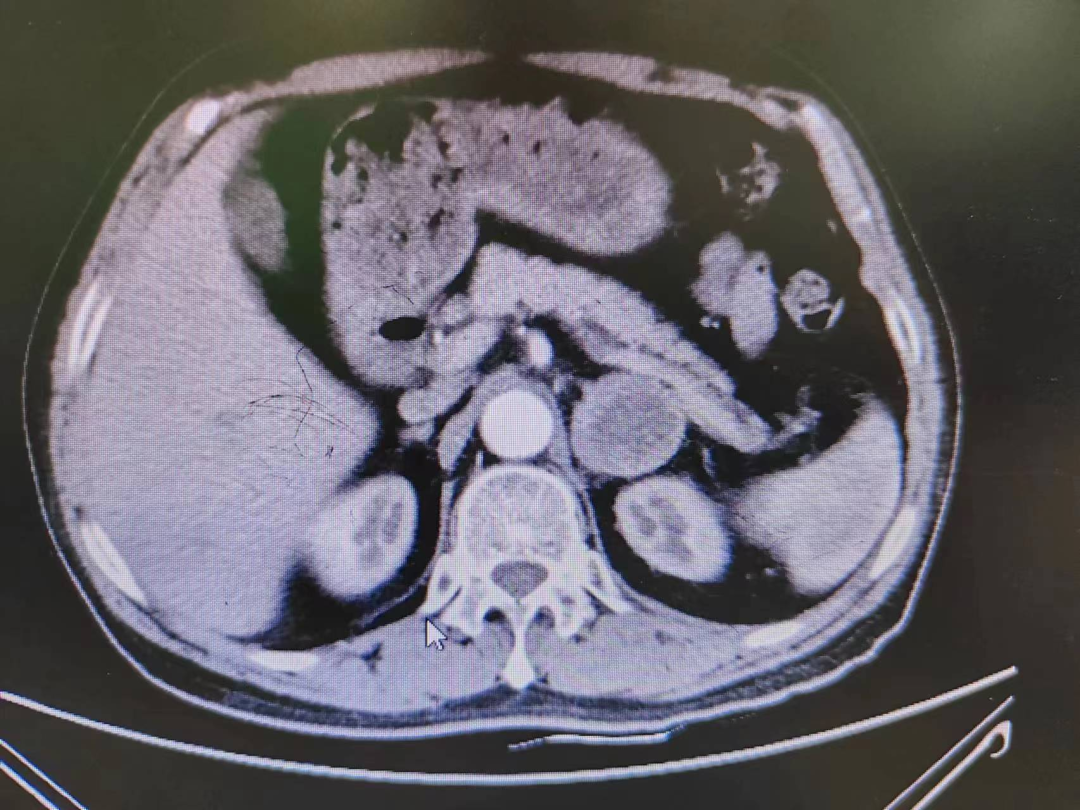

患者熊XX,67歲,因發(fā)現(xiàn)頭暈、頭痛曾多次于外院就診,到新橋醫(yī)院就診完善腎上腺CT考慮嗜鉻細胞瘤,既往有高血壓病史3年,血壓更高達230/120mmHg。我院高新區(qū)院區(qū)開診后,患者慕名而來。術(shù)前積極完善血尿兒茶酚胺代謝產(chǎn)物(MNS)均明顯升高,患者于我院高新區(qū)院區(qū)及江南院區(qū)泌尿外科積極控制血壓、心率、血糖,術(shù)前充分擴容。

因腫瘤位置位于腎蒂周圍,術(shù)中觸碰腫瘤導致血壓明顯升高,血壓波動較大,腫瘤表面血供豐富,不僅需要手術(shù)醫(yī)生豐富的臨床經(jīng)驗和高超的技術(shù)水平,也是對醫(yī)生心理素質(zhì)、勇氣和毅力的嚴峻考驗。

經(jīng)過泌尿外科醫(yī)師全體討論,在進行術(shù)前準備2-3周后,再次請多學科討論評估手術(shù)風險,并與患者及家屬充分溝通后于6月30日行腹腔鏡下左側(cè)腎上腺嗜鉻細胞瘤切除術(shù)。手術(shù)在陳勇主任醫(yī)師的指導下,由孫偉副主任醫(yī)師主刀及王傳麟醫(yī)師完成,術(shù)中見腫瘤與腎蒂血管周圍粘連緊密,與腎動脈、腎靜脈分界不清,稍有不慎,可能損傷腎蒂血管可能需要行腎切除術(shù),且分離腫瘤過程中血壓波動較大。但在孫偉精準操作及分離下,與麻醉醫(yī)生和手術(shù)護士團隊密切配合,經(jīng)過2小時的手術(shù),順利切除嗜鉻細胞瘤,并保護好腎臟血管及周圍組織。術(shù)后患者順利出院,術(shù)后血壓及血糖控制良好。